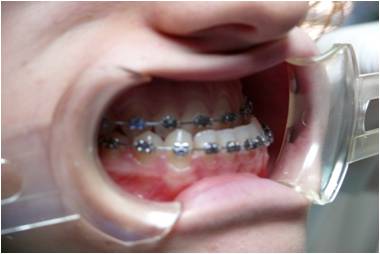

Ortodonzia pubblica

Il trattamento ortodontico è suddivisibile in Ortodonzia intercettiva e dell'età adulta in base al grado di sviluppo scheletrico del paziente.

La terapia intercettiva ha lo scopo di correggere disarmonie di natura prevalentemente scheletrica che, se non trattate tempestivamente, possono evolvere ed aggravarsi nel corso del tempo. I dispositivi ortodontici possono essere di tipo rimovibile o fisso in base alle singole fasi terapeutiche.

Nel caso in cui le problematiche scheletriche non dovessero essere state intercettate durante le fasi di crescita il paziente necessita di trattamento ortodontico-chirurgico atto alla correzione completa dei difetti sia scheletrici che dentali.

Presso i nostri centri è disponibile il servizio specialistico di ortodonzia pubblica rivolto a pazienti in che presentano gravi dismorfie osse che vanno trattati con terapia intercettiva prima o con terapia ortodontico-chirurgica poi.

![]() | ![]() |